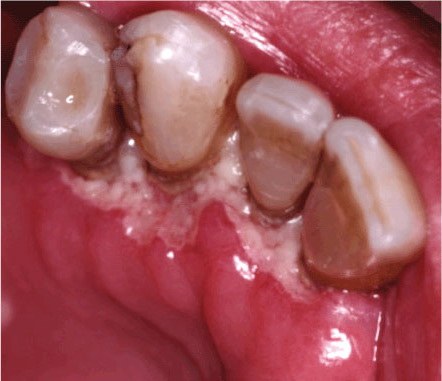

Гингивит может возникать, как в результате грибкового процесса, так и при бактериальном инфицировании. Выделяют маргинальный гингивит (краевая гингивальная эритема), при которой слизистая оболочка, покрывающая край десны, гиперемирована, отечна, напряжена. Язвенно-некротическая форма заболевания характеризуется прогрессированием процесса с изъязвлением и некрозом десневых сосочков и маргинальной десны. При осмотре выявляется некротическая пленка (чаще серо-желтого цвета), покрывающая край десны. Возможны кровотечения, как спонтанные, так и при чистке зубов. Это состояние отмечается у пациентов с выраженной иммунной супрессией [15,23]. Язвенно-некротический гингивит выявлен нами у 74%ВИЧ-инфицированных в стадии СПИД.